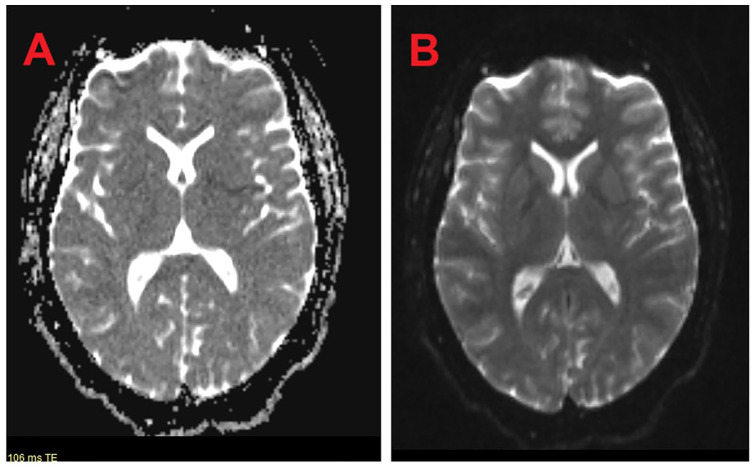

We describe a 30-year-old Caribbean-Black woman with a clinical presentation suggestive of a transient ischemic attack (TIA) with no conventional cerebrovascular risk factors, albeit with a newly diagnosed quadricuspid aortic valve (QAV) with moderate aortic regurgitation (AR). Although QAV is a recognized congenital cardiac defect, its association with TIA remains elusive. This case highlights the importance of considering potential atypical etiologies, such as QAV, in the evaluation and management of young patients presenting with cerebrovascular events.

Abstract Image